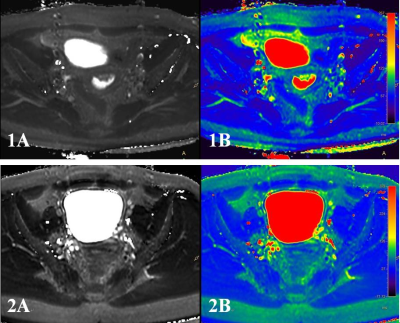

Figure1: 1A. the T2WI image of a 66 years old woman with endometrial carcinoma; 1B. the T2mapping image with measuredT2 value of 66.755 ms;2A.the T2WI image of a 54 years old woman with endometrial polyps;2B. the T2mapping image with measuredT2 value of 94.940 ms.